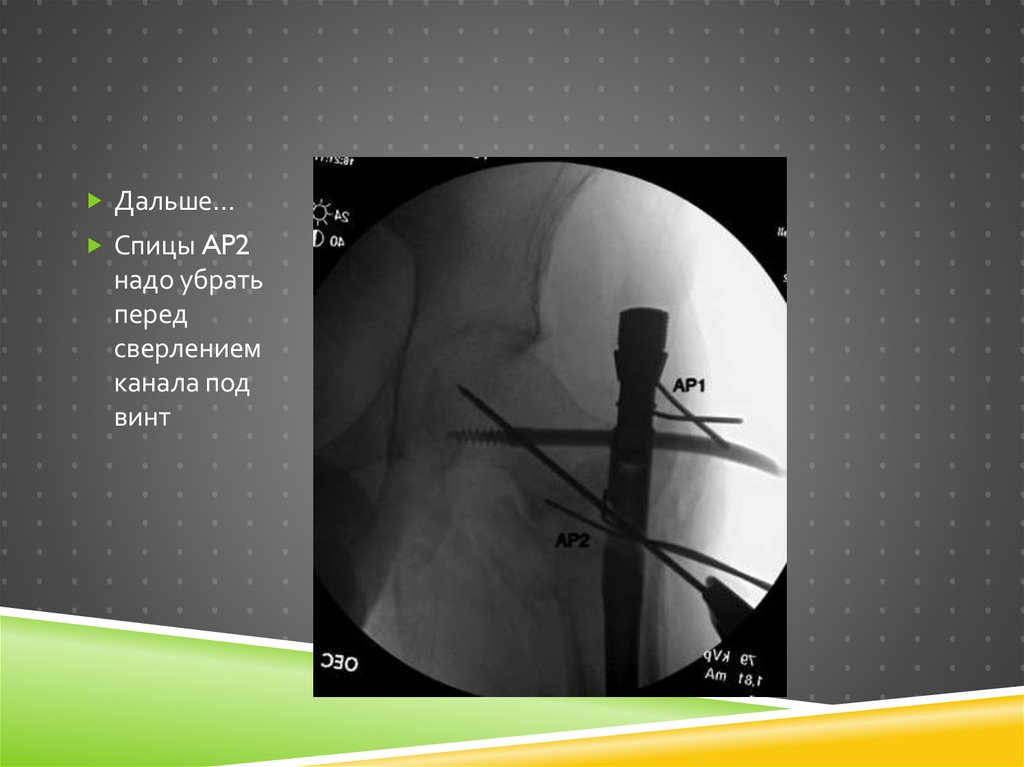

Дальше…

Спицы AP2

надо убрать

перед

сверлением

канала под

винт